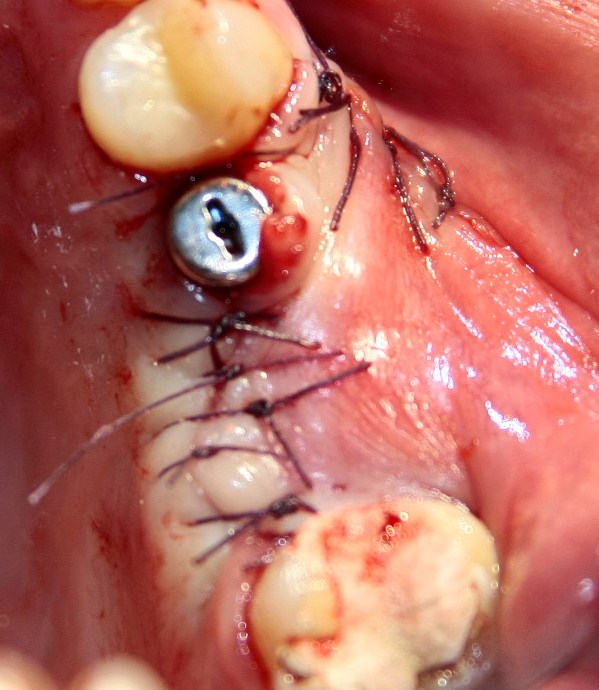

Немедленная имплантация — оптимальное решение в любой клинической ситуации